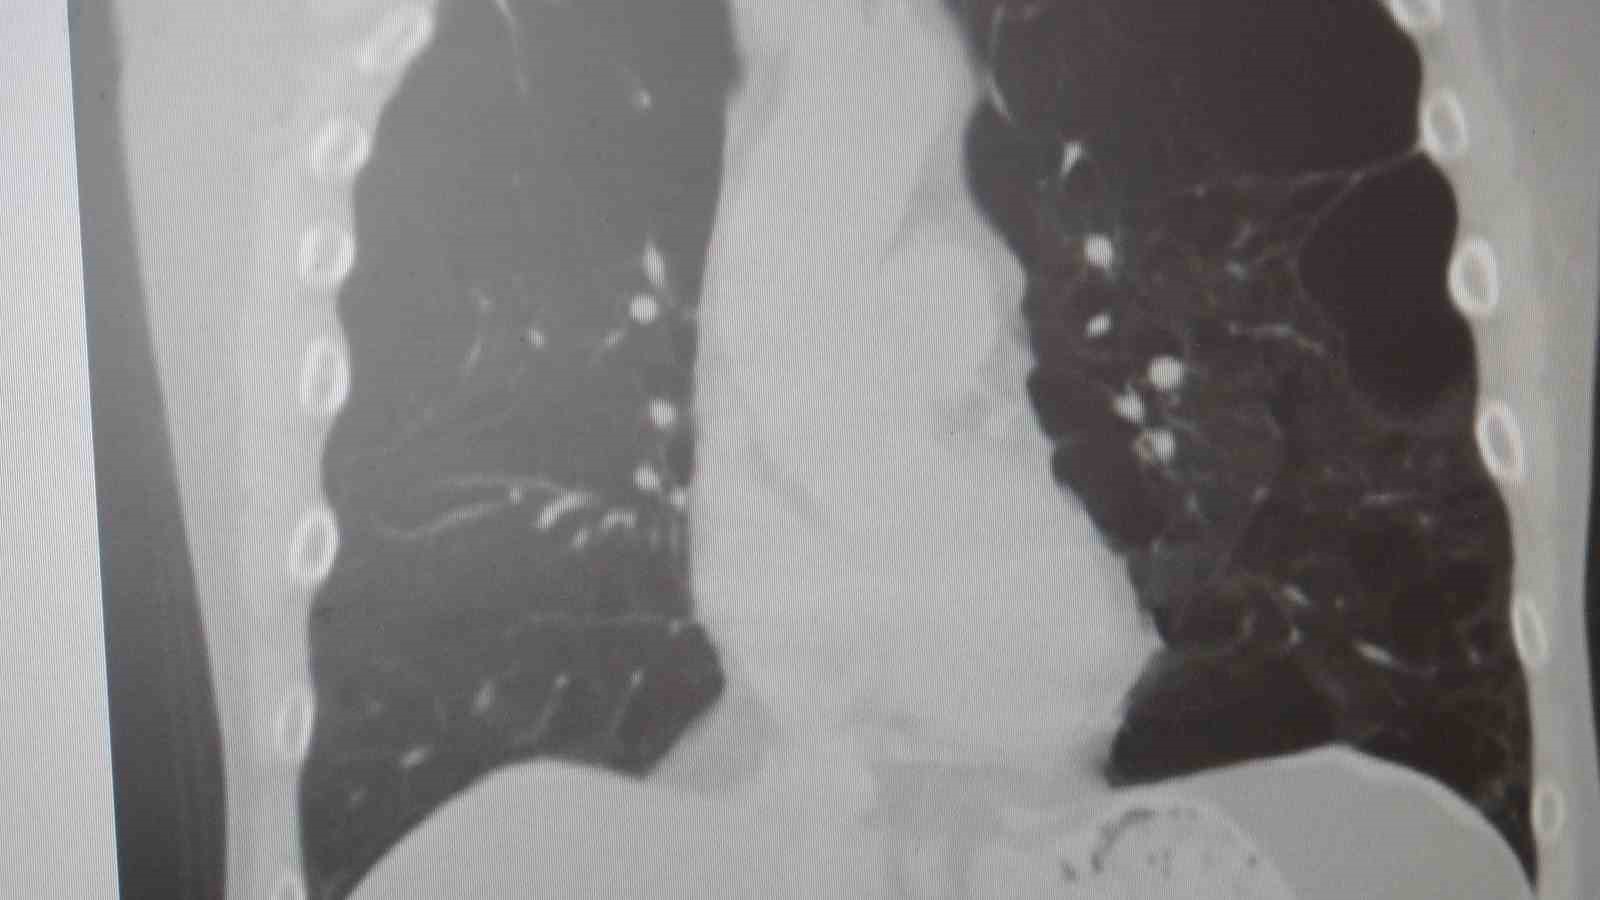

Marmara Üniversitesi Pendik Eğitim ve Araştırma Hastanesi Göğüs Hastalıkları Kliniği’nden Prof. Dr. Sait Karakurt, toplumda sık görülen Kronik Obstrüktif Akciğer Hastalığı (KOAH) ve zatürre hakkında önemli uyarılarda bulundu. KOAH’ın ölümcül hastalıklar listesinde üst sırada yer alan ve toplumda sık görülen bir rahatsızlık olduğunu dile getiren Karakurt, "Vakaların yaklaşık yüzde 85’i sigara kullanımına bağlı" dedi.

Marmara Üniversitesi Pendik Eğitim ve Araştırma Hastanesi uzmanlarından Prof. Dr. Sait Karakurt, dünya genelinde can kayıplarına neden olan hastalıklar arasında 4’üncü sırada yer alan KOAH ve beraberinde getirdiği zatürre riskine karşı önemli açıklamalarda bulundu. Vakaların yüzde 85’inin sigara kullanımı kaynaklı olduğunu vurgulayan Karakurt, KOAH’ın önlenebilir bir hastalık olduğunun altını çizerken; özellikle 65 yaş üstü ve risk grubundaki bireylerin zatürreye karşı aşılama ve erken teşhis konusunda hassas olmaları gerektiğini belirtti.

"KOAH toplumda sık görülen bir hastalıktır ve yaklaşık toplumda bunu yüzde 10 civarında görüyoruz. KOAH, zararlı maddelerin akciğeri parçalamasıyla oluşan bir rahatsızlık ve bunun da en önemli nedeni sigara. Vakaların aşağı yukarı yüzde 85’i sigara kullanımından kaynaklıdır. Bunun dışında hava kirliliği, iş yerlerinde kimyasal maddelere maruz kalma ve enfeksiyonlar da yine KOAH’ın nedenleri arasındadır. KOAH’ın önemi şu; bugün Dünya Sağlık Örgütü’nün (DSÖ) dünyada insanları öldüren hastalıklar listesinde ilk 10’da 4’üncü sırada yer alıyor. KOAH önlenebilir bir rahatsızlıktır; sigaranın bırakılmasıyla birlikte tamamen ortadan kalkacaktır."